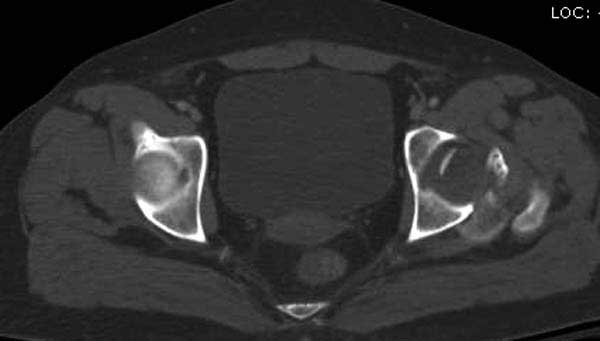

В диагноз еще необходимо внести закрытую (?) ротационно-нестабильную травму таза с переломами лонных седалищных костей, боковой массы крестца справа.

Трудно выбрать приоритет, когда имеется одинаковые по значимости, по сложности повреждения и с вовлечением различной локализации. У пожилых переломо-вывих головки бедра можно было бы проигнорировать, но у молодых такое решение привело бы к катастрофе, и поэтому приоритет первичной фиксации отдали решению переломо-вывиха таранной кости и головки бедра.

Больная стабильная после хирургических мероприятии и получив добро, приступили к закрытому вправлению таранной кости с укладкой наружного фиксатора. Затем укладка больную на бок и открытый остеосинтез перелома-вывиха головки бедра.

По характеру повреждения головка находится сзади и напрашивается задний Кохер-Лангенбек доступ, но в заднем доступе имеется риск повреждения магистрального кровоснабжения головки a. circumflexa. Более щадящая trochanteric flip (digastric osteotomy) сохранит кровоснабжение и дасть возможность работу при вывихнутом суставе.